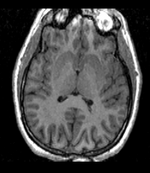

this is the fixed T1 reference image. lleft

• fixed : T1w axial, 0.9375 x 0.9375 x 1.5 mm axial, 256 x 256 x 124

unregistered unregistered after BSpline non-rigid registration afterAffine+ fast BSpline non-rigid registration